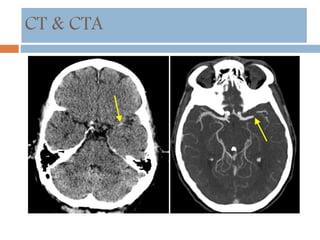

CT & CTA

 HDMCA sign

 Insular ribbon sign

 Sulci effacement

 Lentiform obscuration